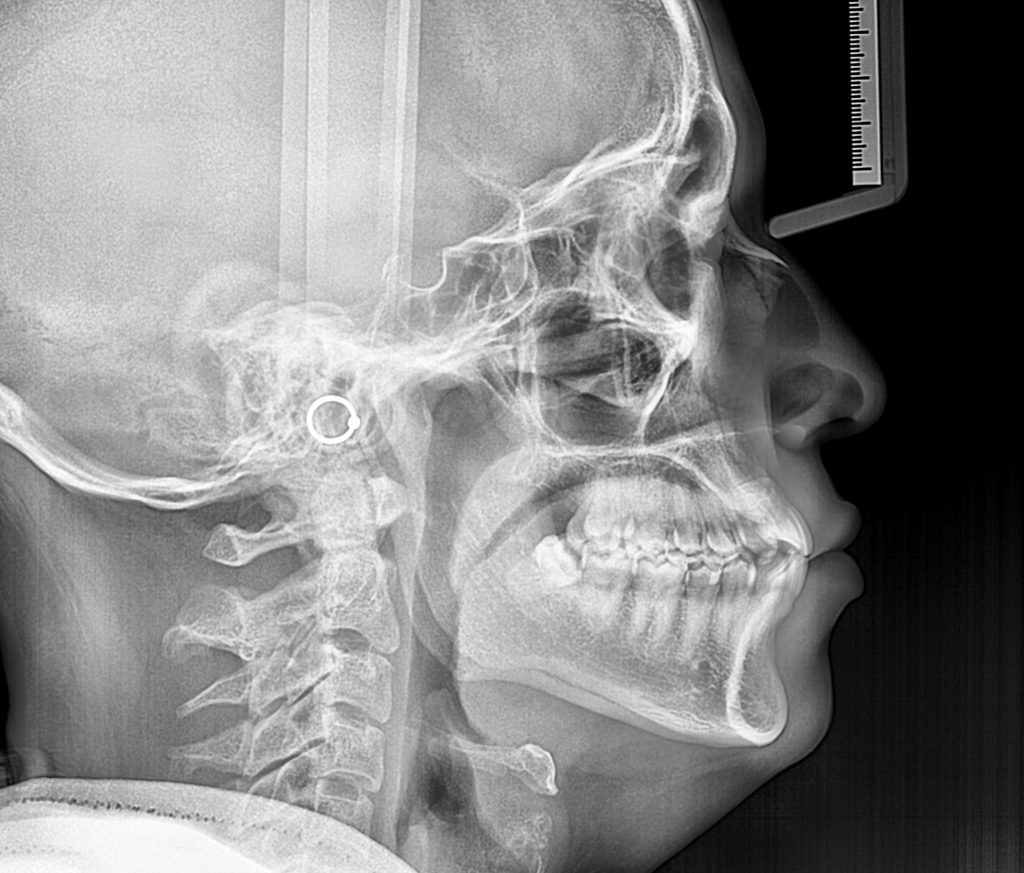

Contamos con el primer y único equipo de Rayos X digital de la ciudad.

Para diagnosticar y tratar las enfermedades orales de manera más eficaz y precisa a nuestros pacientes, y así otorgarles una atención integral y segura, evitándoles viajar cientos de kilómetros a otras ciudades para la toma de estos exámenes. Nuestro equipo de rayos x cuenta con todas las autorizaciones sanitarias para su instalación y desempeño.